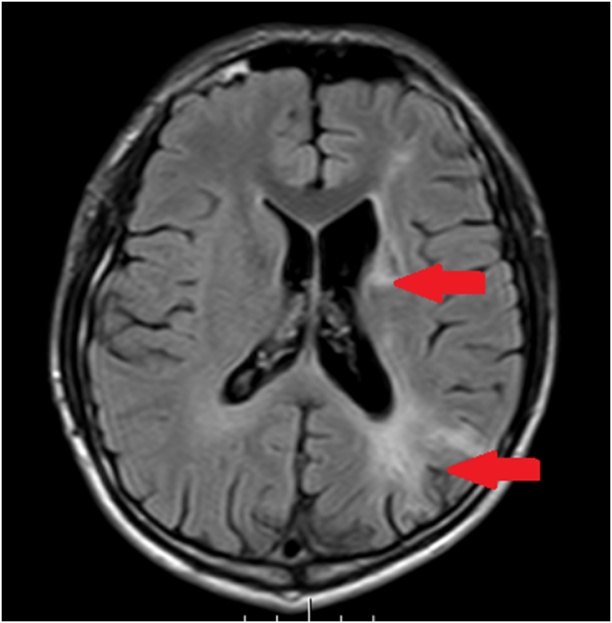

MRI提示:左侧额颞顶枕叶、基底节、侧脑室、胼胝体多发脑梗死。

“检查发现患者大脑左侧多发梗死灶,影响了对侧肢体的支配能力及语言功能。”结合患者的症状和相关检查结果,该院神经内二科主任钟水生诊断其为脑梗死。